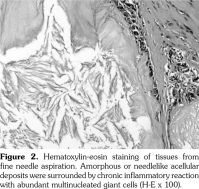

A 54-year-old male patient was admitted to our department with palmar numbness and disability for two years. He had a history of gout for 30 years but received no treatment. Physical examination revealed obvious subcutaneous tophi and thenar muscle wasting. Flexion deformity of his metacarpophalangeal and interphalangeal joints is shown in Figure 1a. Positive Tinel’s sign and Phalen’s maneuver were present. Routine laboratory test showed high level of uric acid (608 μmol/L). The electrophysiological examination revealed sensory and motoring demyelinating and axon lesions in both median nerve, especially in the right hand, which supported the diagnosis of CTS. Furthermore, DECT showed extensive monosodium urate crystals in the intercarpal and radiocarpal joints with compression overlying the flexor tendons (Figure 1b, c). We also observed punched-out bony erosions in the carpal bones (Figure 1d). These aspects indicated severe and typical CTS caused by gouty tophi, which was further confirmed by biopsy of fine-needle aspiration (Figure 2). Surgery was recommended, but the patient refused to undergo surgery and chose to receive febuxostat. Uric acid level had decreased in the next six-month follow-up with little improvement for his numbness and deformity. A written informed consent was obtained from the patient.